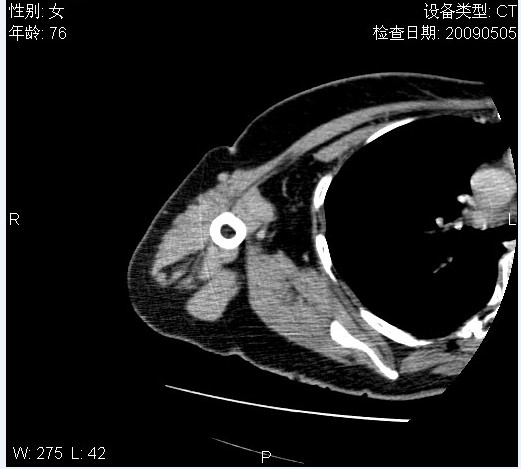

标题: CT19811:女,76岁,右上臂肿物1个月 [打印本页]

标题: CT19811:女,76岁,右上臂肿物1个月

使用了造影剂,可惜效果不太好

右肱骨上段软组织内见梭形低密度影,边界清楚,最长径约54mm.

病理结果:脂肪瘤。术中见肱骨骨膜受侵,有出血,量不详。

当时诊断意见:右肩三角肌内蔓状血管瘤(先天性动静脉瘘)。

本人对病理结果有个疑问:单纯的脂肪瘤内为什么有条状软组织影,那应该脂肪肉瘤才对啊?

该病例增强效果欠佳,由于经验欠缺,我们注射对比剂是由下肢足背静脉给药。注速2.0。虽然如此,但我们可以看到肿块内部条状软组织影是强化的,而且是连续的,并可见供血动脉是由腋动脉的其中一支即肩胛下动脉分出。从这些征象我们可以得出诊断:蔓状务血管瘤。

可病理偏偏为脂肪瘤,我怀疑取材有问题。因为蔓状血管瘤异常扩张的静脉外周是脂肪成分,它可以侵犯肌组织及骨骼。当取材于外周,那当然是脂肪瘤。此时我认为临床的最终诊断不应单从病理出发,应该综合考虑。